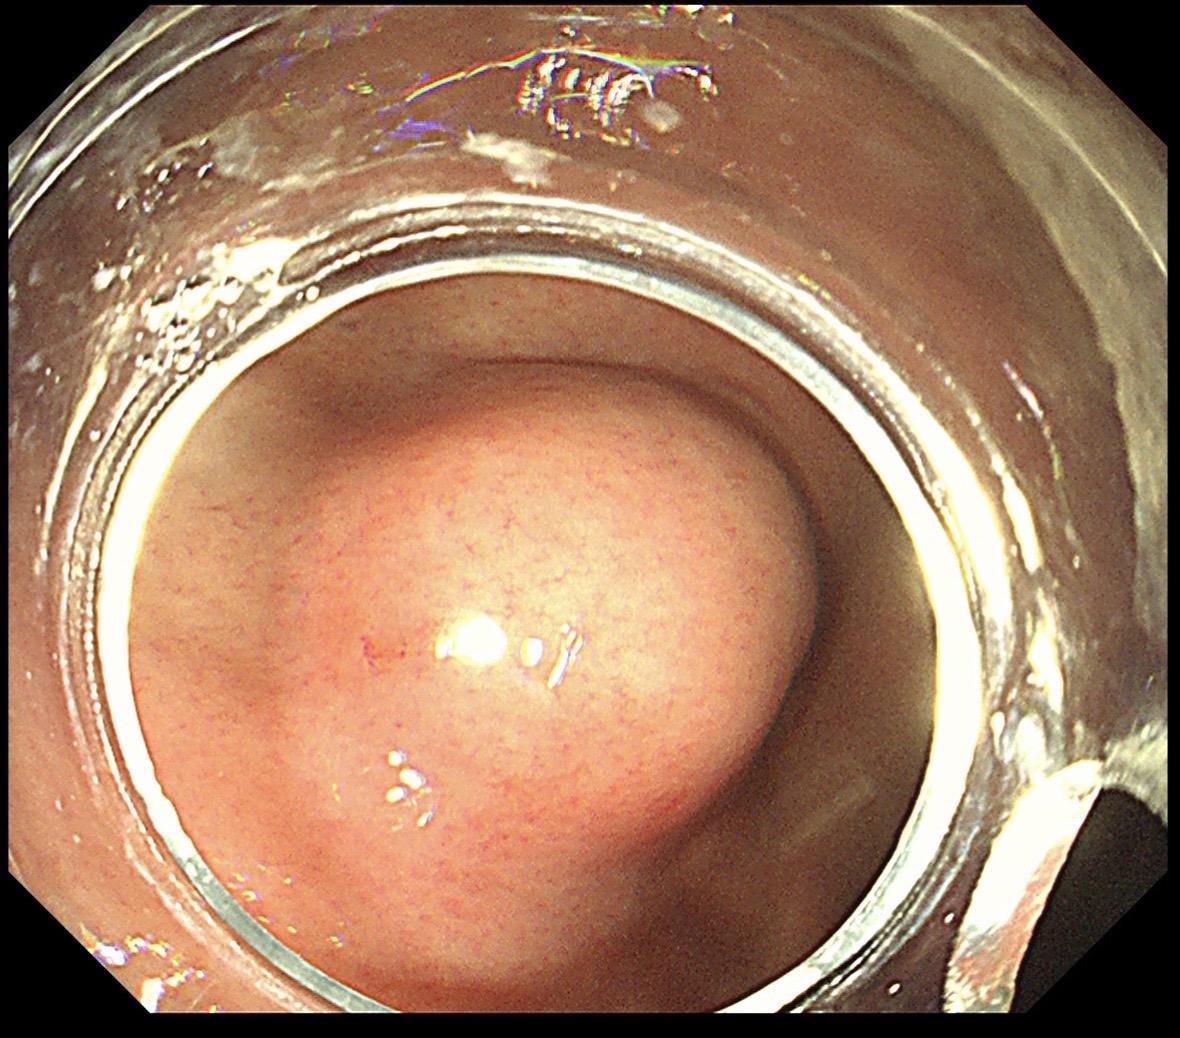

胃黏膜下隆起都是间质瘤吗?不是的!这个很像间质瘤的胃黏膜下隆起,其实是...